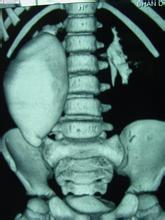

超音波、CT、MRI檢查可明確區分增大的腎是積水還是實性腫塊亦可發現壓迫泌尿系統的病變,由於超聲檢查已經普及且為無創傷性,可以在尿路造影以前進行。放射性核素掃描和腎圖亦可用於腎積水的診斷。對動力性梗阻病例,可在尿路造影是觀察腎盂、輸尿管蠕動及排空情況。神經原性膀胱可見膀胱造影形似"寶塔",有成小梁和假性憩室。